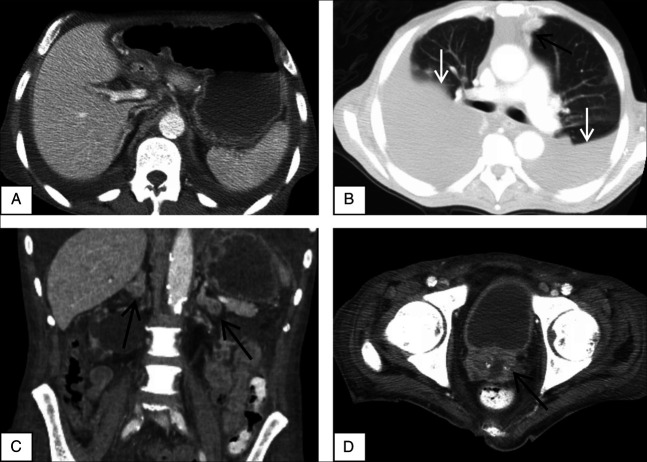

组织胞浆菌病具有广泛的表现,从轻微的肺部疾病到导致播散性组织胞浆菌病的更广泛的感染。胃肠组织浆菌病是一种罕见的播散性组织浆菌病,最常引起非特异性症状,很少出现严重症状。累及十二指肠也很少见,但可引起溃疡性病变,导致上消化道出血。非特异性初始表现可能迅速发展为致命的上消化道出血,因此将胃肠道组织胞浆菌病列入我们的鉴别清单非常重要,因为及时开始适当的抗真菌治疗可以显著降低严重并发症和死亡率的风险。

Histoplasmosis has a wide spectrum of presentations ranging from mild pulmonary disease to a more widespread infection leading to disseminated histoplasmosis. Gastrointestinal histoplasmosis is a rare form of disseminated histoplasmosis that most commonly causes nonspecific symptoms and rarely presents with serious symptoms. Duodenal involvement is further rare but can cause ulcerated lesions leading to upper gastrointestinal bleed. The potential for a nonspecific initial presentation quickly progressing to a fatal upper gastrointestinal bleed makes it important to keep Gastrointestinal histoplasmosis in our list of differentials, as timely initiation of appropriate antifungal therapy can significantly reduce the risk of severe complications and mortality.